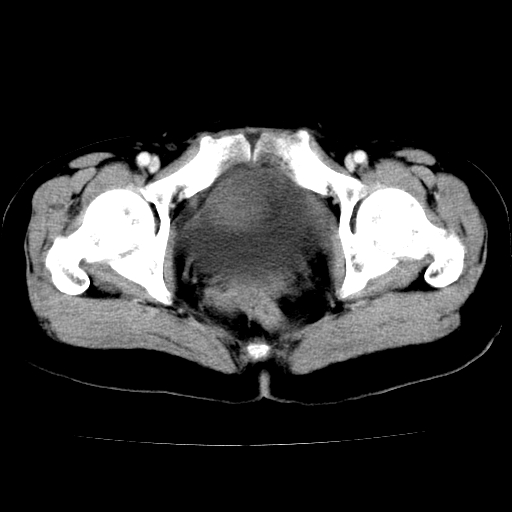

标题: CT24785:女,62岁,发现下腹部肿物半年。 [打印本页]

标题: CT24785:女,62岁,发现下腹部肿物半年。

女,62岁,发现下腹部肿物半年,下腹部不适。

老年女性患者,盆腔囊实性占位,ct增强不均匀强化,未见壁结节,未见腹水及盆腔积液,考虑附件囊腺瘤可能性大!